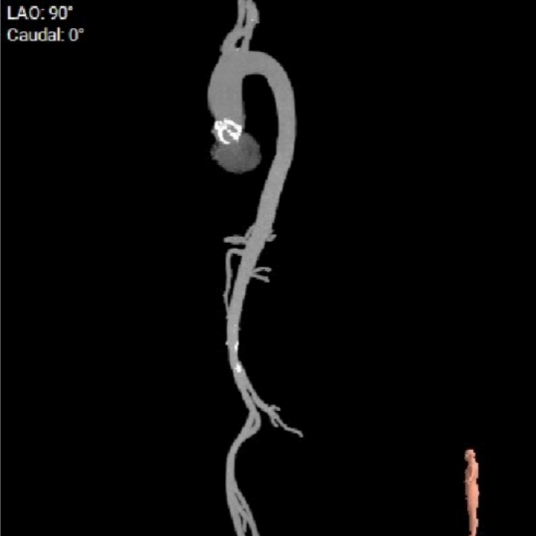

主动脉根部CTA:

根部概览:

外周血管及主动脉弓解剖